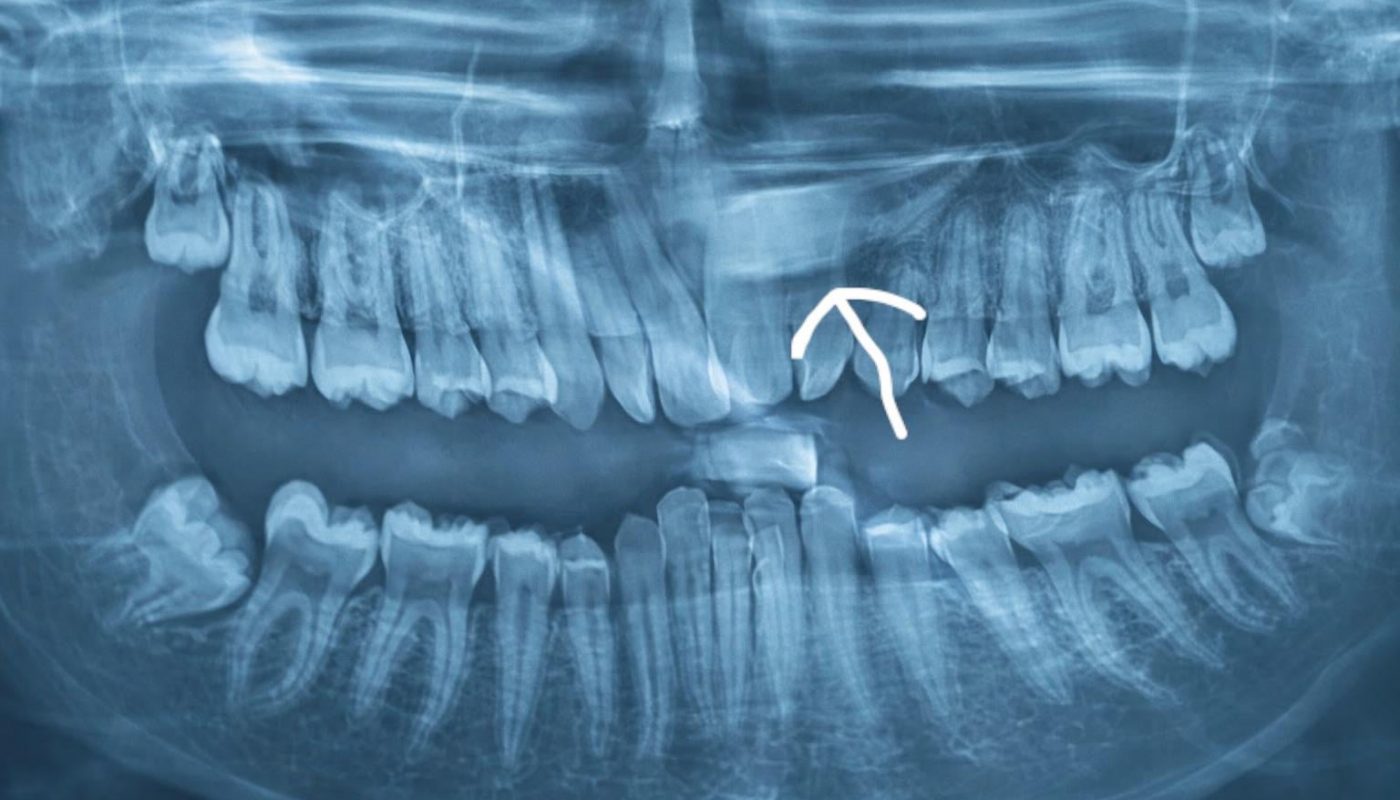

You brush. You floss. You visit the dentist regularly. So how could a tooth be hiding in your gums without you knowing? Surprisingly, many people discover—often by chance—that an adult tooth is “sleeping” peacefully beneath the surface of their gums. This phenomenon, known as an impacted or unerupted tooth, is more common than you might think. In this article, we’ll explore why teeth remain dormant in the jaw, signs to watch for, and what steps to take next to safeguard your smile.

These “sleepers” often go unnoticed until detected via X-rays or symptoms arise.

Impacted teeth affect 20–25% of people, with wisdom teeth (third molars) being the most frequent culprits. However, other teeth—like canines or premolars—can also fail to emerge. Surprisingly, you may never experience pain or swelling, making routine dental exams critical for early detection.

If your dentist suspects an impacted tooth, they’ll use:

- Panoramic X-rays: Show the entire jaw and hidden teeth.

- 3D Imaging: Creates a detailed map of bone structure and tooth angles.